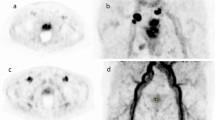

Of note, the SUVmean uptake of 68Ga-SC691 in the liver was lower than that of 68Ga-PSMA-11: 2.5 ± 0.7 vs. 4.1 ± 1.6 (P = 0.002). This results in improved contrast for visualizing liver lesions in cases of PCa liver metastasis with 68Ga-SC691 (Fig. 6). Although liver metastasis of PCa is a relatively rare late-stage event, the potential for liver involvement is higher when considering the application of PSMA targeting in other tumors, such as breast cancer and renal cell carcinoma. Furthermore, lower radiation absorbed dose to the liver during 177Lu/225Ac-SC691 therapy for PCa is also a noteworthy advantage.

A 63-year-old male patient with a recent diagnosis of prostate cancer (PCa) two weeks prior to imaging and one cycle of goserelin treatment presented with a PSA level of approximately 68.1 ng/mL. (A) 68Ga-SC691 PET/CT MIP image demonstrated high tracer uptake in the primary PCa lesion(red circle), multiple right iliac para-vascular lymph node metastases, and a focal hypermetabolic lesion in the right lobe of the liver consistent with metastasis. (B) Transaxial fused PET/CT images, the liver lesion showed an SUVmax of approximately 6.9, compared to a normal liver parenchyma SUVmean of approximately 3.1. (C) The prostate showed intense and homogenous tracer uptake with an SUVmax of approximately 29.7. (D) 68Ga-PSMA-11 PET/CT MIP image showed similar distribution patterns of tracer uptake(PCa lesion, red circle); however, the liver metastasis was less clearly visualized due to higher background activity in the normal liver parenchyma. (E) The corresponding transaxial fused PET/CT image of the liver showed the lesion with a higher SUVmax of approximately 9.0 (normal liver parenchyma SUVmean ≈ 4.5). (F) The prostate also showed intense uptake with an SUVmax of approximately 35.3. The TBRs for 68Ga-SC691 compared to 68Ga-PSMA-11 were higher for both the liver metastasis-to-normal liver (2.2 vs. 2) and the PCa lesion-to-normal liver (9.58 vs. 7.84), suggesting improved contrast on visual analysis.